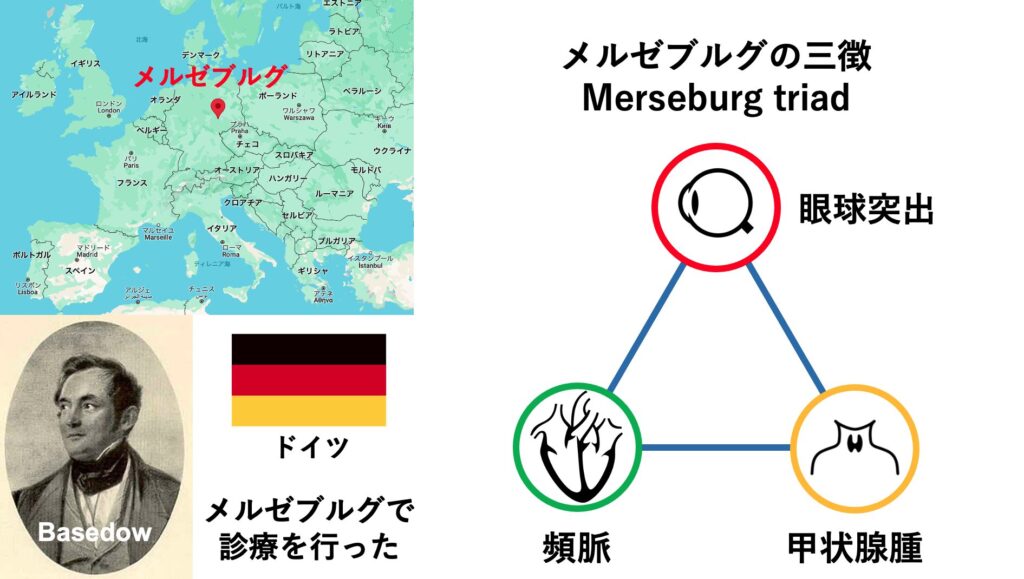

病名は報告者に由来しており、英語圏ではグレーブス病と呼ばれますが、ドイツ医学を取り入れた日本ではバセドウ病と呼ばれます。グレーブスの方が5年早く報告しています。ちなみに2人の報告はネットで読むことができます。(「London Medical and Surgical Journal」、「Wochenschrift für die gesammte Heilkunde」)

バセドウはドイツのメルゼブルグで診療を行っており、バセドウ病患者の特徴として眼球突出・頻脈・甲状腺腫を報告しました。メルゼブルグで見つけた3徴であることから後にメルゼブルグの3徴と呼ばれるようになりました。